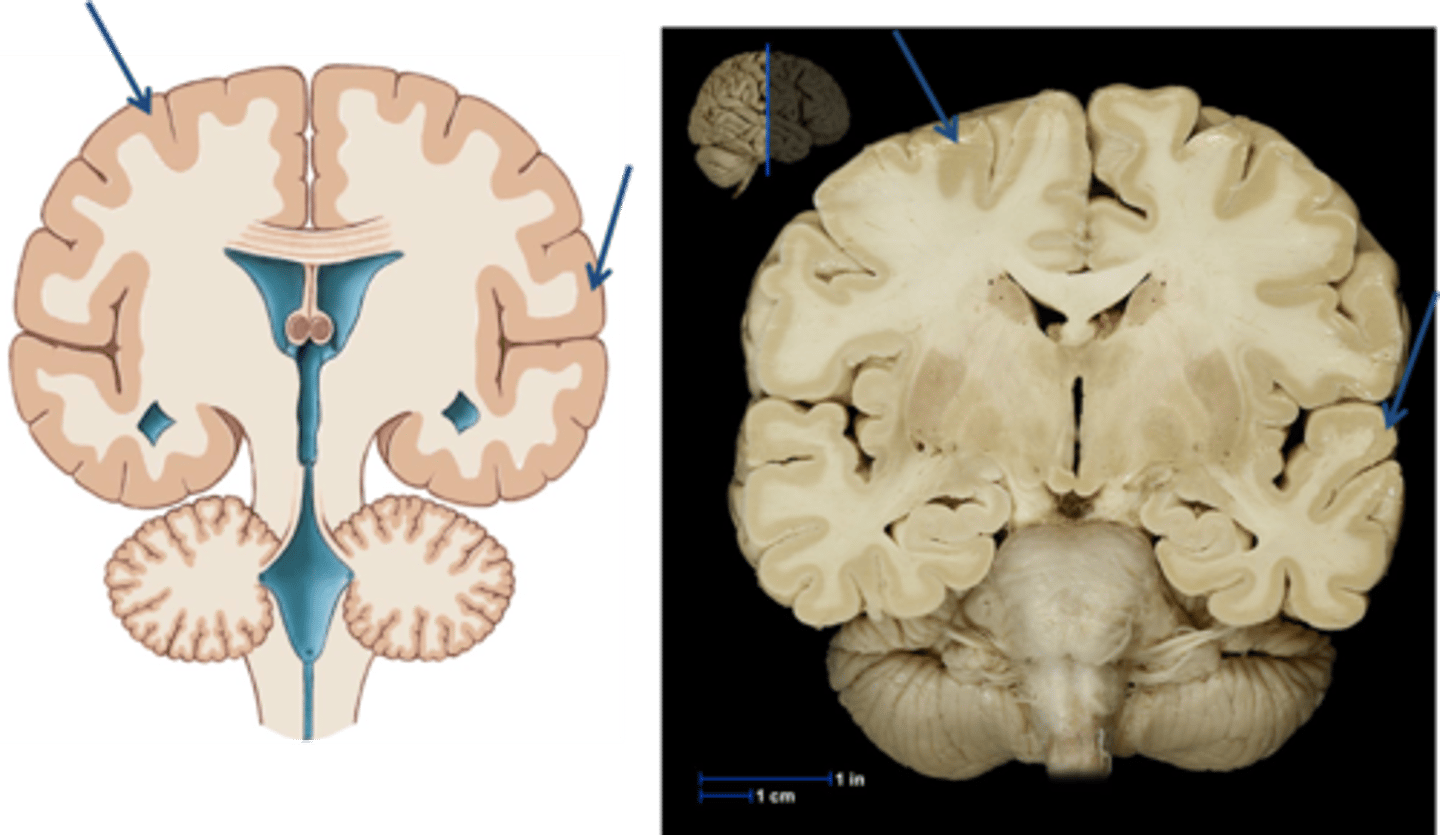

Cerebral cortex

outer region of the cerebrum, containing sheets of nerve cells; gray matter of the brain; the executive suite of the brain, where our conscious mind is found

Gray matter

Brain and spinal cord tissue that appears gray with the naked eye; consists mainly of neuronal cell bodies (nuclei) and lacks myelinated axons.

White matter

Whitish nervous tissue of the CNS consisting of neurons and their myelin sheaths.

Gyrus

Sulcus

brain fissures